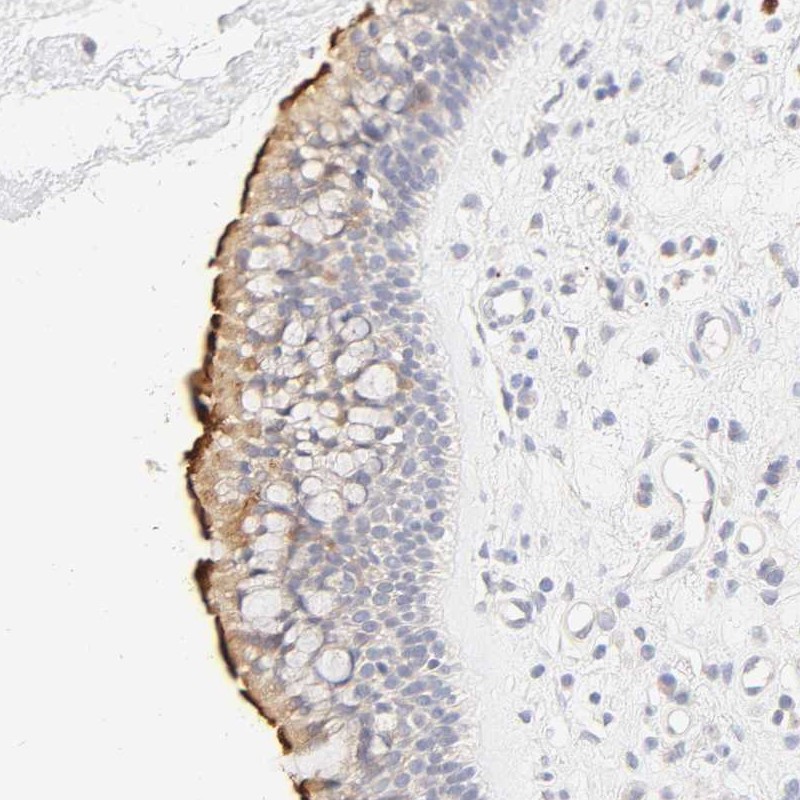

Immunohistochemical staining of human nasopharynx shows strong membranous positivity in respiratory epithelial cells.